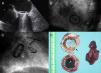

Transesophageal echocardiogram (A) and fluoroscopy (B and C) showing impaired motion of the two leaflets due to associated pannus and thrombosis; (D) explanted mechanical mitral valve. The shape of pannus growth on the ventricular surface of the prosthesis removed from the prosthesis can be clearly seen. The concentric stenosis of the valve orifice area (black arrow) and the thrombosis on the atrial side causing valve blockage (white arrow) are evident. The mural blood clot removed from the left atrial appendage is shown.

A 78-year-old woman with a history of hypertension and diabetes was admitted to our institution with a one-year history of progressive dyspnea. Ten years previously she had been diagnosed with rheumatic heart disease and atrial fibrillation and had undergone mitral valve replacement with a 25-mm Carbomedics bileaflet mechanical valve. She had been asymptomatic until two months ago, when she reported dyspnea (New York Heart Association class III), orthopnea, and weight gain. Physical examination revealed cardiac arrhythmia and signs of decompensated heart failure (ascites and lower limb edema). Laboratory tests showed no abnormalities. The electrocardiogram confirmed atrial fibrillation. An echocardiogram revealed restricted motion of the mitral leaflets (Figure 1A), with partial thrombosis of the mitral prosthesis and a blockage of the posterior mechanical prosthesis disc. A high transmitral gradient was observed by transesophageal echocardiography. A left atrial (LA) mural thrombus, moderately depressed left ventricular ejection fraction (45%), severe pulmonary artery hypertension (systolic pulmonary artery pressure of 70 mmHg), and severe functional tricuspid regurgitation were also detected. A coronary angiogram confirmed an immobile prosthetic leaflet (Figure 1B and 1C). No lesions were seen in the main coronary arteries. The patient was scheduled for cardiac surgery.

Through median resternotomy, adherences from the previous surgery were carefully released. Cardiopulmonary bypass was established with bicaval venous cannulation. Through transseptal access, the mitral prosthesis was accessed and examined. Intraoperatively, a 3×3 cm thrombus was removed from the origin of the left atrial appendage (not closed during the first cardiac operation) and in immediate contact with the mechanical valve (Figure 1D). A partial thrombosis was observed around the mechanical valve and an immobile prosthesis disc was seen. The mitral prosthesis was replaced and the mechanical valve was excised, revealing circumferential mitral prosthesis obstruction due to pannus growing within the valve orifice on the ventricular surface of the prosthesis. The valve was replaced with a 31-mm Labcor mitral bioprosthesis and tricuspid annuloplasty was also performed. Echocardiographic monitoring confirmed that the mitral prosthesis was functioning correctly without leakage after placement. Postoperatively, the patient recovered uneventfully and was discharged home nine days after surgery with greater exercise tolerance and progressive improvement.